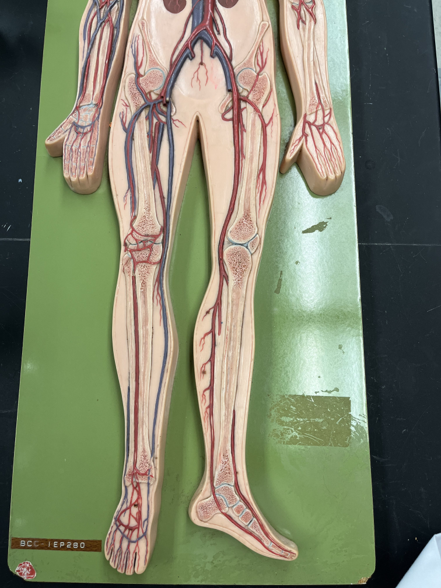

11

New cards

endothelium

• Part of the tunica interna.

• Composes a smooth inner surface of the vessel.

• Composes a smooth inner surface of the vessel.

12

valve

• Found in some veins.

• Establishes unidirectional flow of blood.

• An artery of the head and neck.

• Originates from the brachiocephalic trunk (R.) or the aortic arch (L.).

• Supplies the head and neck through its branches.

• Originates from the brachiocephalic trunk (R.) or the aortic arch (L.).

• Supplies the head and neck through its branches.